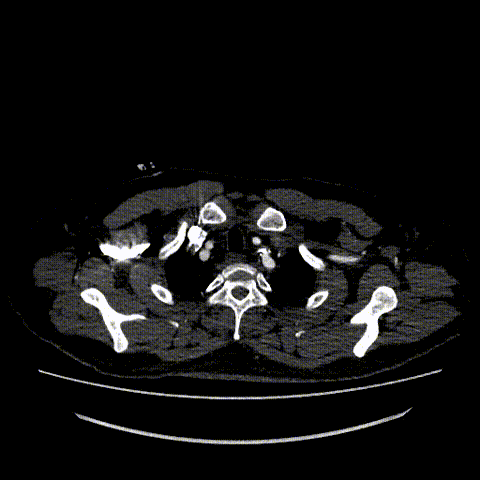

术前CTA:主动脉弓、左锁骨下动脉、胸主动脉附壁血栓伴部分穿透性溃疡。病变位于左锁骨下动脉根部前壁位置,近端锚定区不足

术前CTA横截面

术前CTA:B型主动脉夹层破裂,左侧胸腔大量积血、积液,双肾萎缩